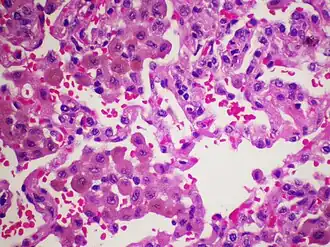

Патоморфология

Ключевым признаком данного заболевания является содержание большого количества макрофагов в просвете альвеол. Альвеолярные перегородки инфильтрированы лимфоцитами, эозинофилами, иногда мезенхимальными клетками, однако, фиброз либо отсутствует, либо выражен не значительно[5]. Поражена практически вся легочная паренхима[3].